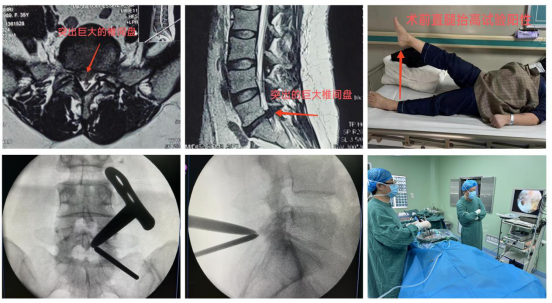

周至县人民医院骨科近期收治了一位35岁女性患者,主诉“右下肢抽痛、麻木半年,加重2月”,行走约50米后,右下肢疼痛难忍,严重影响生活质量。靳占奎副主任医师对患者进行了一系列检查和严格的鉴别诊断,认定该患者“腰椎间盘突出症”诊断明确,且患者经过半年以上的保守治疗无显著疗效,具有明确手术指征。靳占奎副主任医师指导县医院充分完善UBE技术必备的硬件条件,为患者顺利实施了“微创单侧双通道脊柱内镜下腰椎间盘髓核摘除术”。术后患者右下肢疼痛缓解,患者非常满意。

微创单侧双通道脊柱内镜(UBE)技术是治疗腰椎间盘突出症的经典微创手术方式,相较于其它微创手术,该技术入路更接近开放手术,学习曲线相对平缓,镜下视野更全面,操作通道可以应用类似开放手术的器械,安全性高。该手术目前是六合彩网站

骨科脊柱微创手术治疗的一大特色。